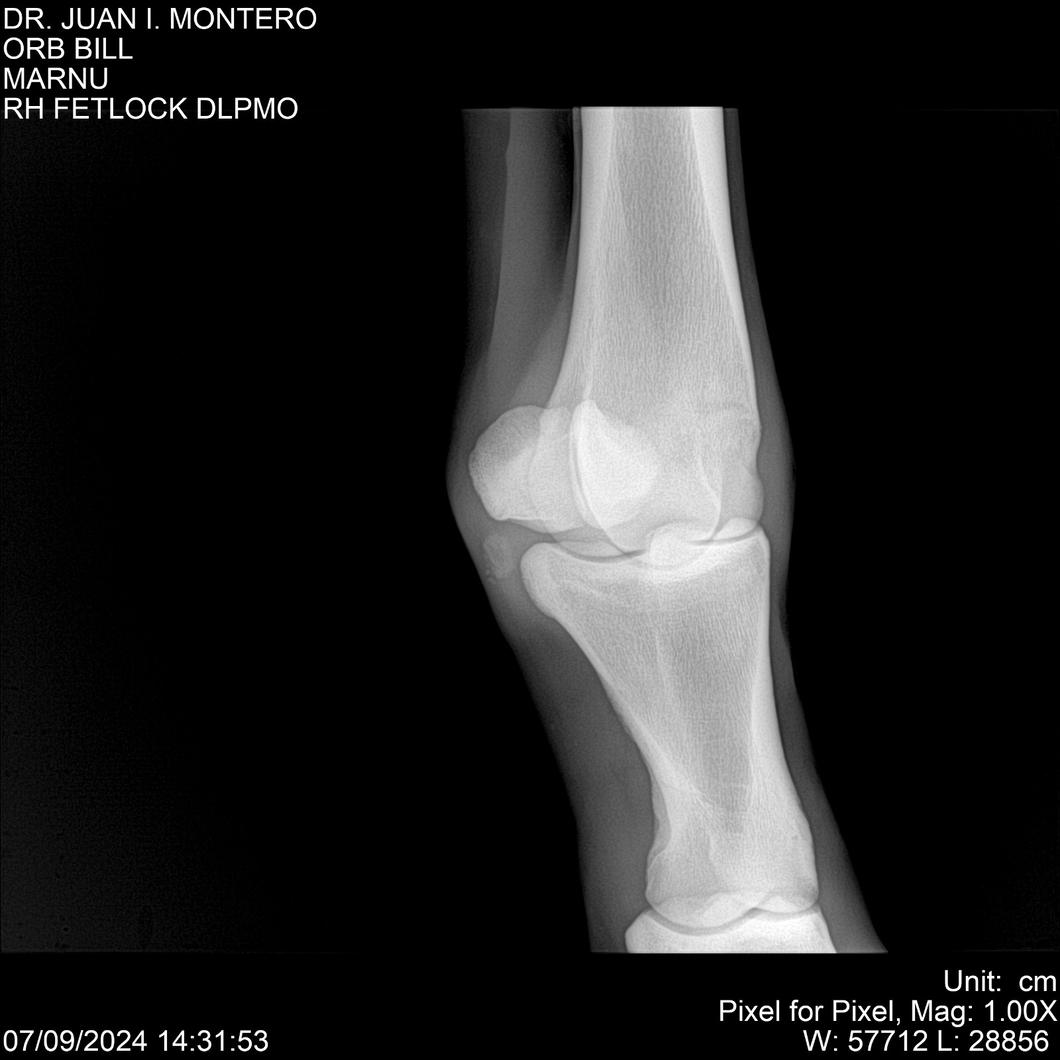

LOTE 7, ORB BILL 🔥 🔥 🔥 Lote Anterior Volver al remate Lote Siguiente Ficha Contacto Montevideo - Ficha del Lote Identificador: #282523 Categoría: Yeguarizos Montevideo - 83 Visualizaciones ClicData Contacto Empresa: Abelenda N. R., Walter Hugo Nombre*: Teléfono* : E-mail* : Mensaje Enviar Registrese gratis Este contenido Exclusivo está disponible sólo para usuarios registrados Ingresar